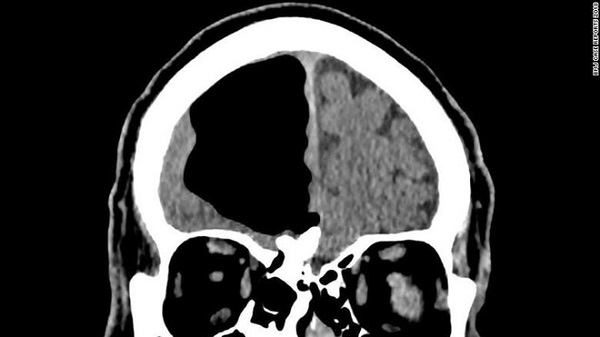

Chỉ sau khi bệnh nhân được đưa đi chụp cắt lớp vi tính (CT) và cộng hưởng từ (MRI), đội ngũ bác sĩ mới phát hiện tình trạng đáng báo động: Đầu của người đàn ông này bị rỗng một lỗ ở vị trí bên phải, nơi mà lẽ ra ở đó nên có nhiều thùy não đang tồn tại.

Ảnh chụp não của người đàn ông bị bệnh khí nội sọ

Nhưng ngay cả những bệnh nhân bị khí nội sọ, khoảng trống trong đầu họ thường nhỏ hơn rất nhiều. Theo báo cáo trên tạp chí BMJ Case Reports, người đàn ông 84 tuổi có một khoang khí dài tới gần 9cm trong hộp sọ.

Vùng đầu bên phải của người đàn ông 84 tuổi có một khoang khí nội sọ